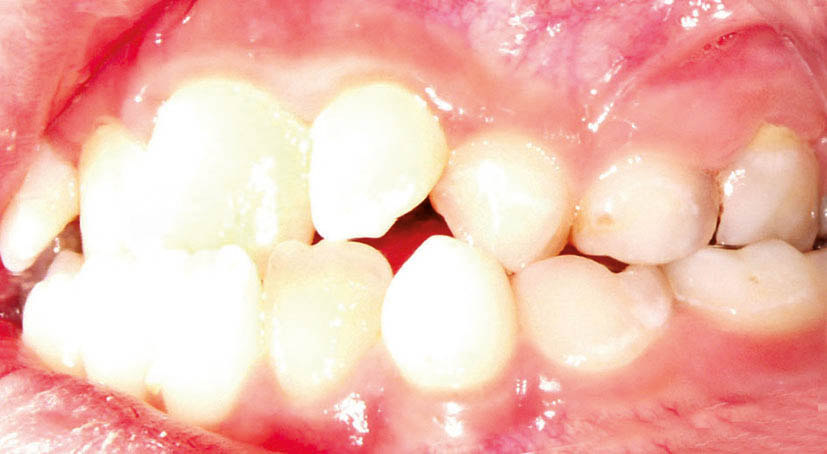

بعضی موقع چند مشکل را با هم در یک کودک میبینید. مثلاً بیمار کراس خلفی یک طرفه و کراس قدامی (شکل 36-5 و 37-5) دارد.

شکل 36-5: کراس بایت خلفی در سمت چپ

شکل 37-5: سمت راست کراس بایت خلفی ندارد پس کودک کراس بایت خلفی یک طرفه دارد.